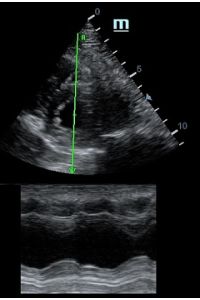

Оценка кооптации нижней полой вены ещё никогда не была такой простой и точной, никаких лишних деталей, просто устанавливаем клипер по анэхогенному участку.